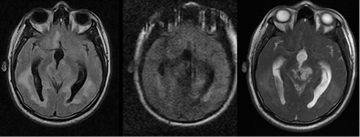

Imagen 4 Imágenes heterogéneas, cambios en sustancia blanca periventricular apreciada en ponderación FLAIR (imagen izquierda); en imagen de ponderación DWI con restricción a la difusión (imagen Imagen 5a. 10X Imagen 5b.40X central), en secuencia FIESTA se observa lesiones hiperintensas con visualizacionde tabiques y contenido heterogéneo.